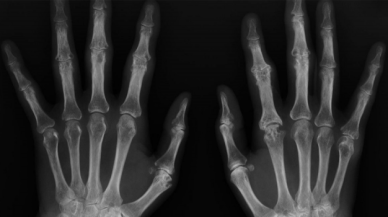

Kemik Yaşı Haberleri

Son Dakika Kemik Yaşı Haberleri

Bu sayfada güncel gelişmeleri takip edenler için Kemik Yaşı ile ilgili en son gelişmeler ve son dakika Kemik Yaşı haberleri sunulmaktadır. Kemik Yaşı videoları, Kemik Yaşı fotoğrafları ve Kemik Yaşı haberleri